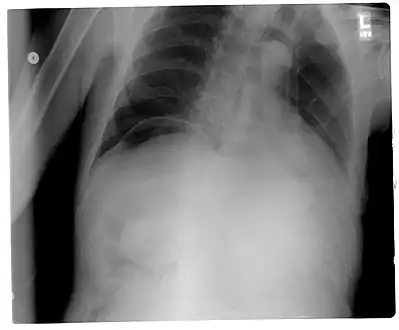

Frontal chest X-ray. The air bubble below the right hemidiaphragm (on the left of the image) is a pneumoperitoneum.

When present, pneumoperitoneum can often be seen on projectional radiography, but small amounts are often missed, and CT scan is nowadays regarded as a criterion standard in the assessment of a pneumoperitoneum.[18] CT can visualize quantities as small as 5 cm³ of air or gas.

Signs that can be seen on projectional radiography are shown below:

As differential diagnoses, a subphrenic abscess, bowel interposed between diaphragm and liver (Chilaiditi syndrome), and linear atelectasis at the base of the lungs can simulate free air under the diaphragm on a chest X-ray.